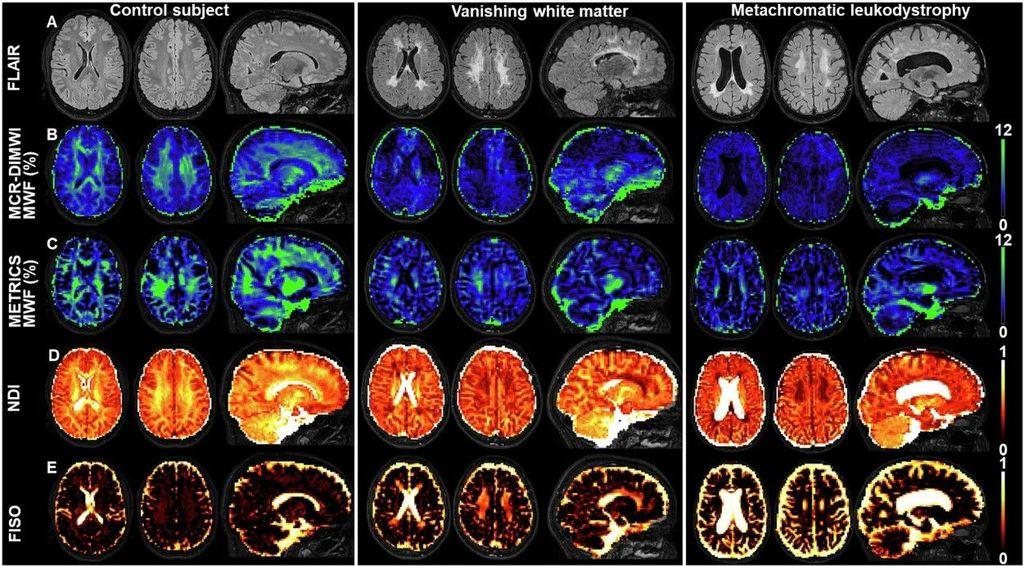

Join Loukas G. Astrakas as he dives into the future of leukodystrophy diagnosis, exploring the potential of new techniques, including quantitative MRI (qMRI). Could the integration of qMRI improve our diagnosis, monitoring, and treatment of patients with leukodystrophies?

Commentary πŸ‘‰ rdcu.be/d00eZ

Original Article πŸ‘‰ buff.ly/3U4UrCj